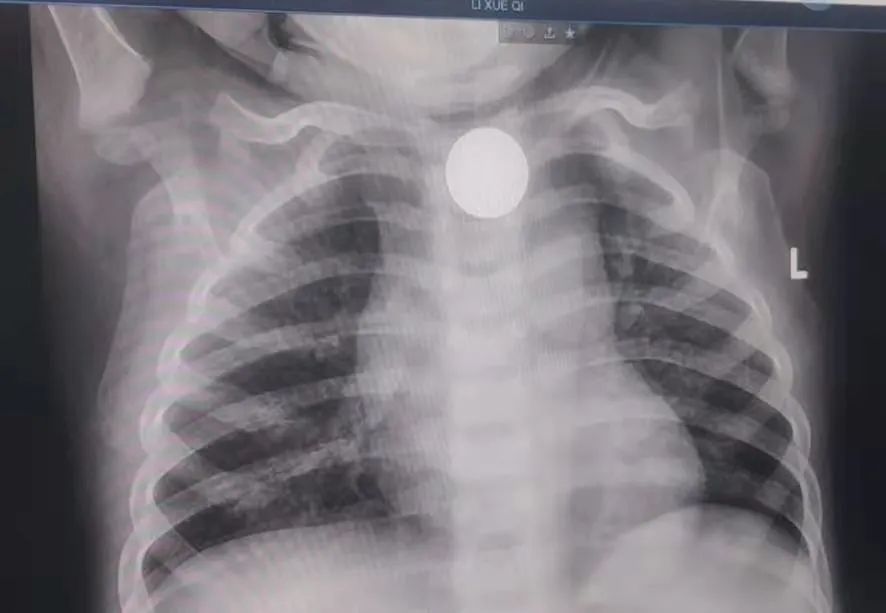

进修结束返院后李佳和冯琦在儿科大主任高春燕及消化内科大主任刘鹏飞、胃镜室主任马莹的大力支持下,积极开展工作,目前已独立完成了小儿胃镜检查 20 余例,联合消化内科在手术室行无痛胃镜下异物取出术,顺利取出一枚 1 角硬币,用时 2 分钟。